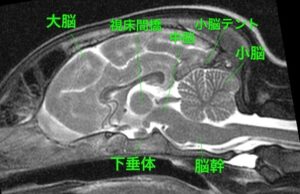

・脳に発作を起こすような異常は見られず

・脳脊髄液(脳や神経のまわりを流れる液)

の異常も認められない

<MRIって?>

MRIは磁気共鳴画像診断とも呼び、強力な磁力と電波により臓器や血管などを画像化する検査